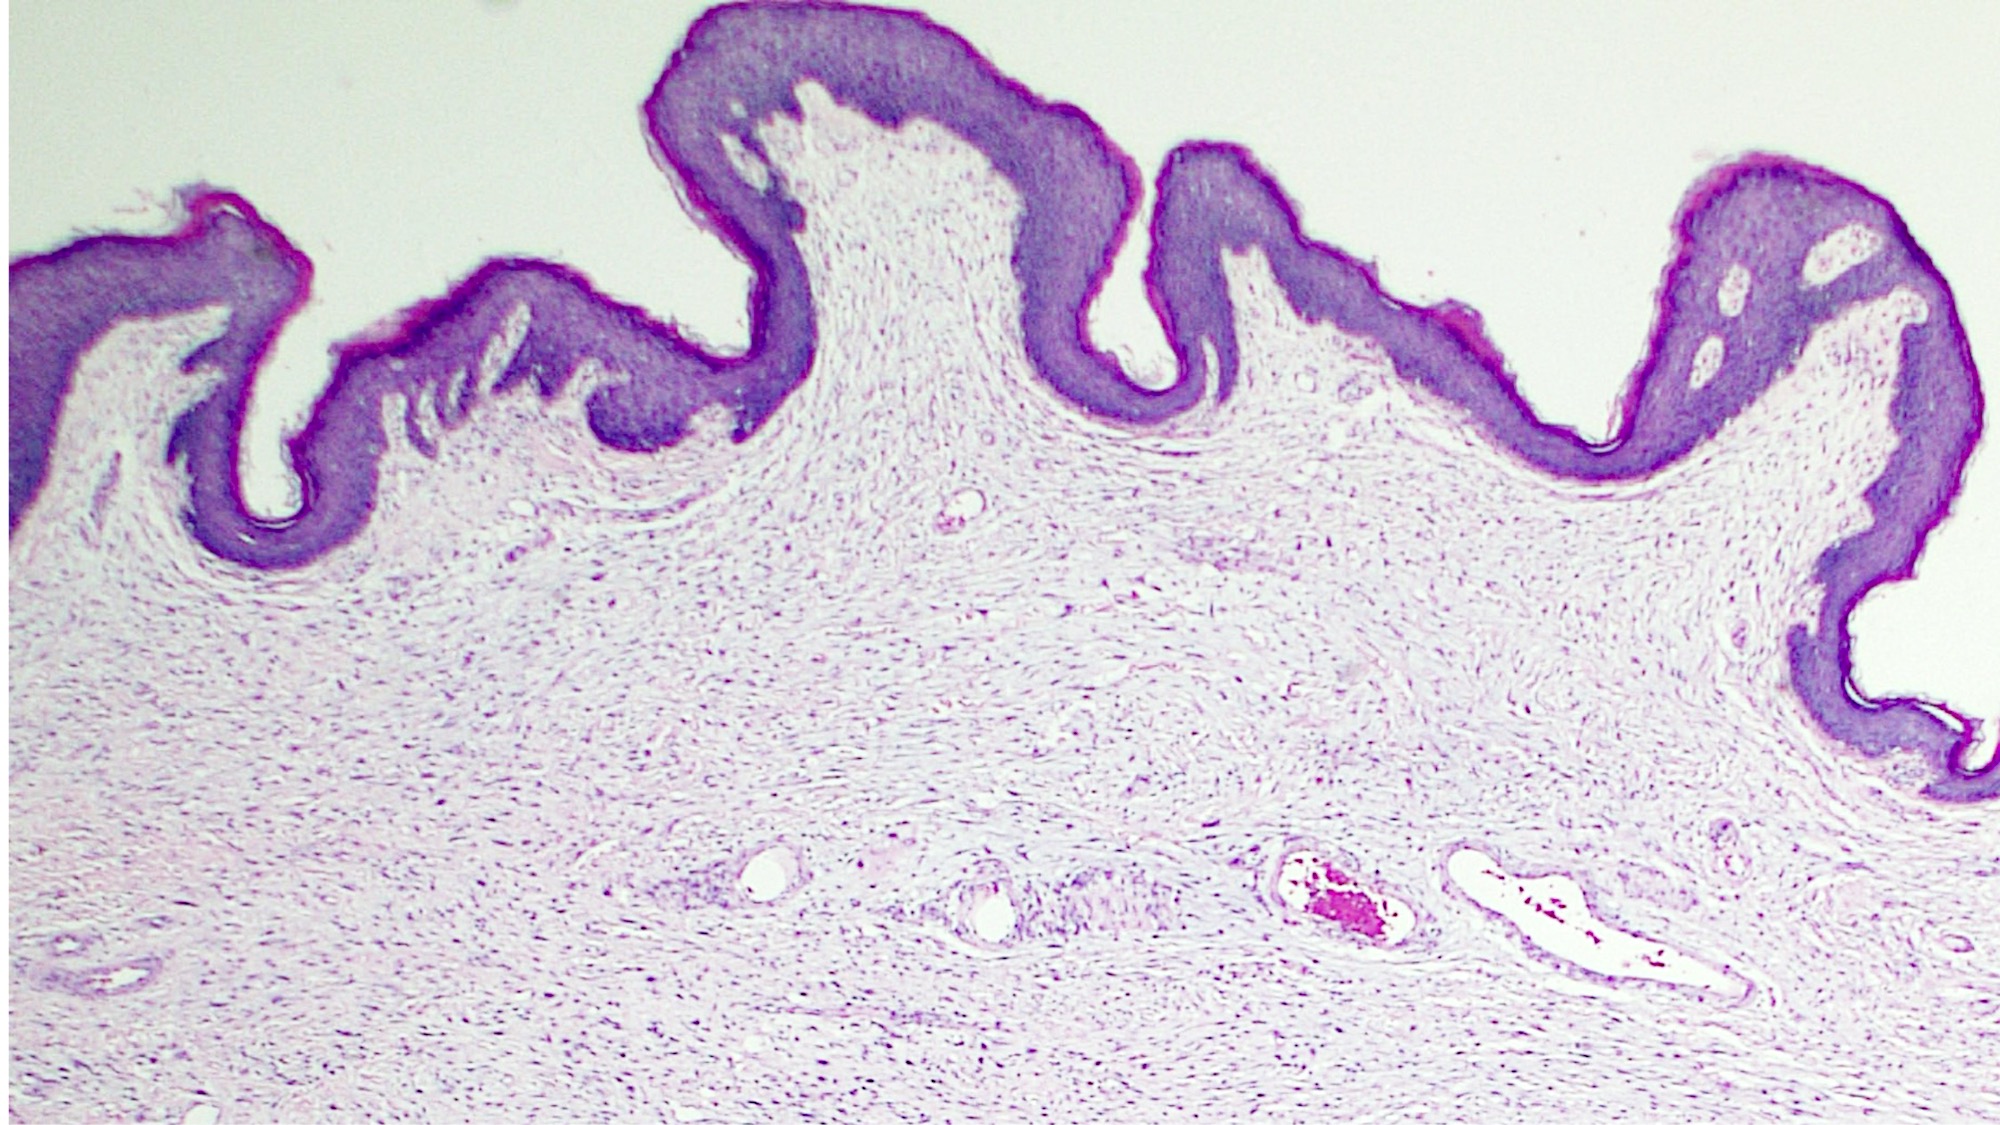

Microscopic (histologic) description

- Polypoid and noncircumscribed, extending to the epithelial / subepithelial interface (J Low Genit Tract Dis 2011;15:69, Am J Surg Pathol 2000;24:231)

- 2 stromal cellularity variants: hypocellular form (spindle cells set within a loose collagenous myxoid-like stroma) or hypercellular variant (exhibits marked nuclear pleomorphism and frequent mitoses, including atypical forms), especially during pregnancy, therefore mimicking leiomyosarcoma or rhabdomyosarcoma (Am J Surg Pathol 2000;24:231)

- Overlying squamous epithelium may display reactive changes but without papillomatous architecture or koilocytosis, which distinguishes it from condyloma acuminatum (caused by human papillomavirus) (Am J Surg Pathol 2005;29:460)

- Stellate cells should not be interpreted as sarcoma (J Low Genit Tract Dis 2011;15:134)

- Commonly found around blood vessels or near the epidermal stromal interface

Microscopic (histologic) images

- A 25 year old woman presented with a vulvar mass, measuring 3.0 cm in diameter. The lesion was excised and the H&E image is shown. Which of the following is the most likely diagnosis?